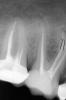

Денис481 Опубликовано 17 июля, 2013 Поделиться Опубликовано 17 июля, 2013 ну подскажите пожалуйста,работаю мтухами,протейперы разлюбил из за хрупкости..,а сегодня поломал и м ту,блин не пойму,может что не так делаю,я работаю 1 ковровые дорожки патфайлами,2 замеряю длинну канала 3 от белого 15 м ту до красного 25 (ну конечный размер бывает разным) на всю р д прохожу,мою после каждого размера,использую рс преп для машинных,сегодня уже прошел канал белым,помыл,опять думаю белым залезу бах,сломался.... торг 09,скорость 250.....вот как он может обломиться......достать не смог,но обошел..... Ссылка на комментарий

Денис481 Опубликовано 17 июля, 2013 Автор Поделиться Опубликовано 17 июля, 2013 (изменено) длина рабочей части какая? 16 или 21 мм?21,ибо 16 не доходил,до апекса,а вообще есть и те и те,и отдельно для распломбировки мту,еще по поводу сушки,как вы сушите каналы,слышал что с "пистолета"нельзя,и видел раз что происходит,а пинами очень долго,вы как это делаете??? Изменено 17 июля, 2013 пользователем Денис481 Ссылка на комментарий

Каплан Опубликовано 17 июля, 2013 Поделиться Опубликовано 17 июля, 2013 21 мм и есть причина поломок. Они испытывают большую нагрузку, чем 16. Быстрее раскручиваются. Во всяком случае мо моим ощущениям и по моему опыту. Если 10ку с рабочей частью 16 мм я погу использовать в 10-12 каналах, то с рабочей 21 мм в 8 максимум. Они нужны только в резцах и клыках. В остальных длина канала от устья до апекса редко бывает больше 16 мм. Сушить- канюлю от метапасиы в канал, к канюле подставляете пылесос. Количесво пинов в 2 раза меньше точно. Ссылка на комментарий